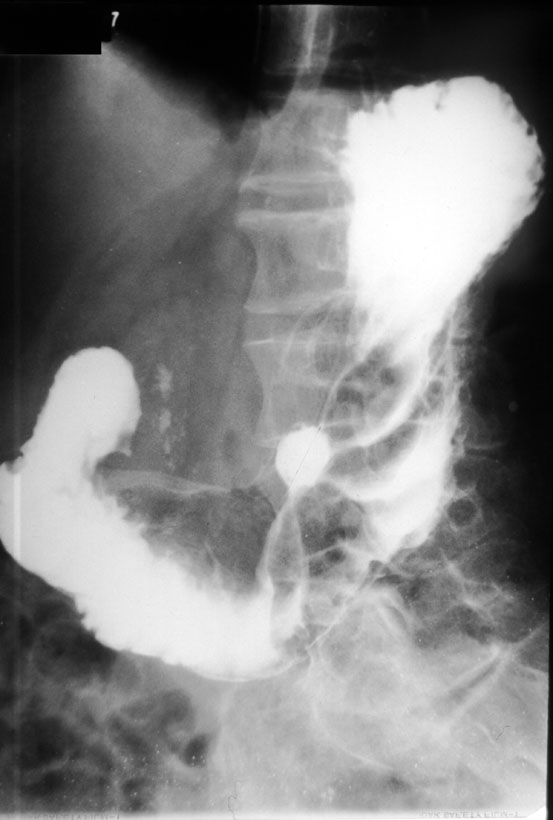

Симптом язвенной ниши

Симптом язвенной ниши 119 фото